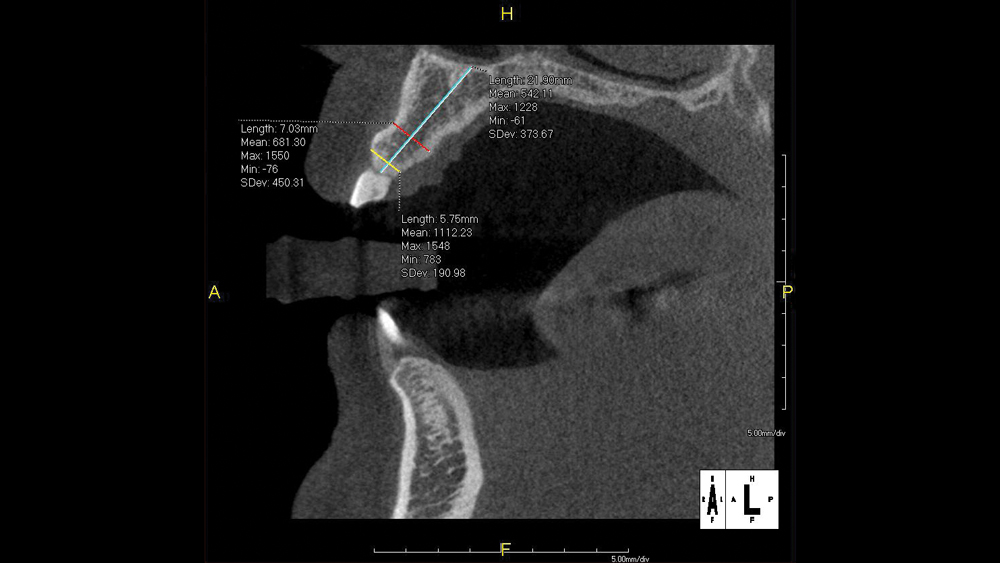

The benefits of CBCT scanning, digital treatment planning and digitally guided implant surgery are well-established. After determining the ideal implant position based on a 3D scan and the restorative goals, a surgical guide is fabricated to precisely transfer the digital treatment plan to the patient’s mouth. The surgical procedure is completed with great efficiency, reducing the chair time required to place an implant. Due to the clinical advantages of this approach, digitally guided surgery is utilized both by experienced practitioners seeking to optimize their results and by newcomers to implant placement, who benefit from increased safety and confidence.

The following case illustrates the efficient, straightforward clinical workflow for placing Hahn Tapered Implants via guided surgery. A digital treatment plan is developed in which a 3.5 mm implant is positioned to support the ideal prosthetic outcome. An immediate provisional crown is designed in concert with the surgical guide and delivered at the time of surgery, helping to produce a predictable, highly esthetic restoration for a demanding case in the smile zone.